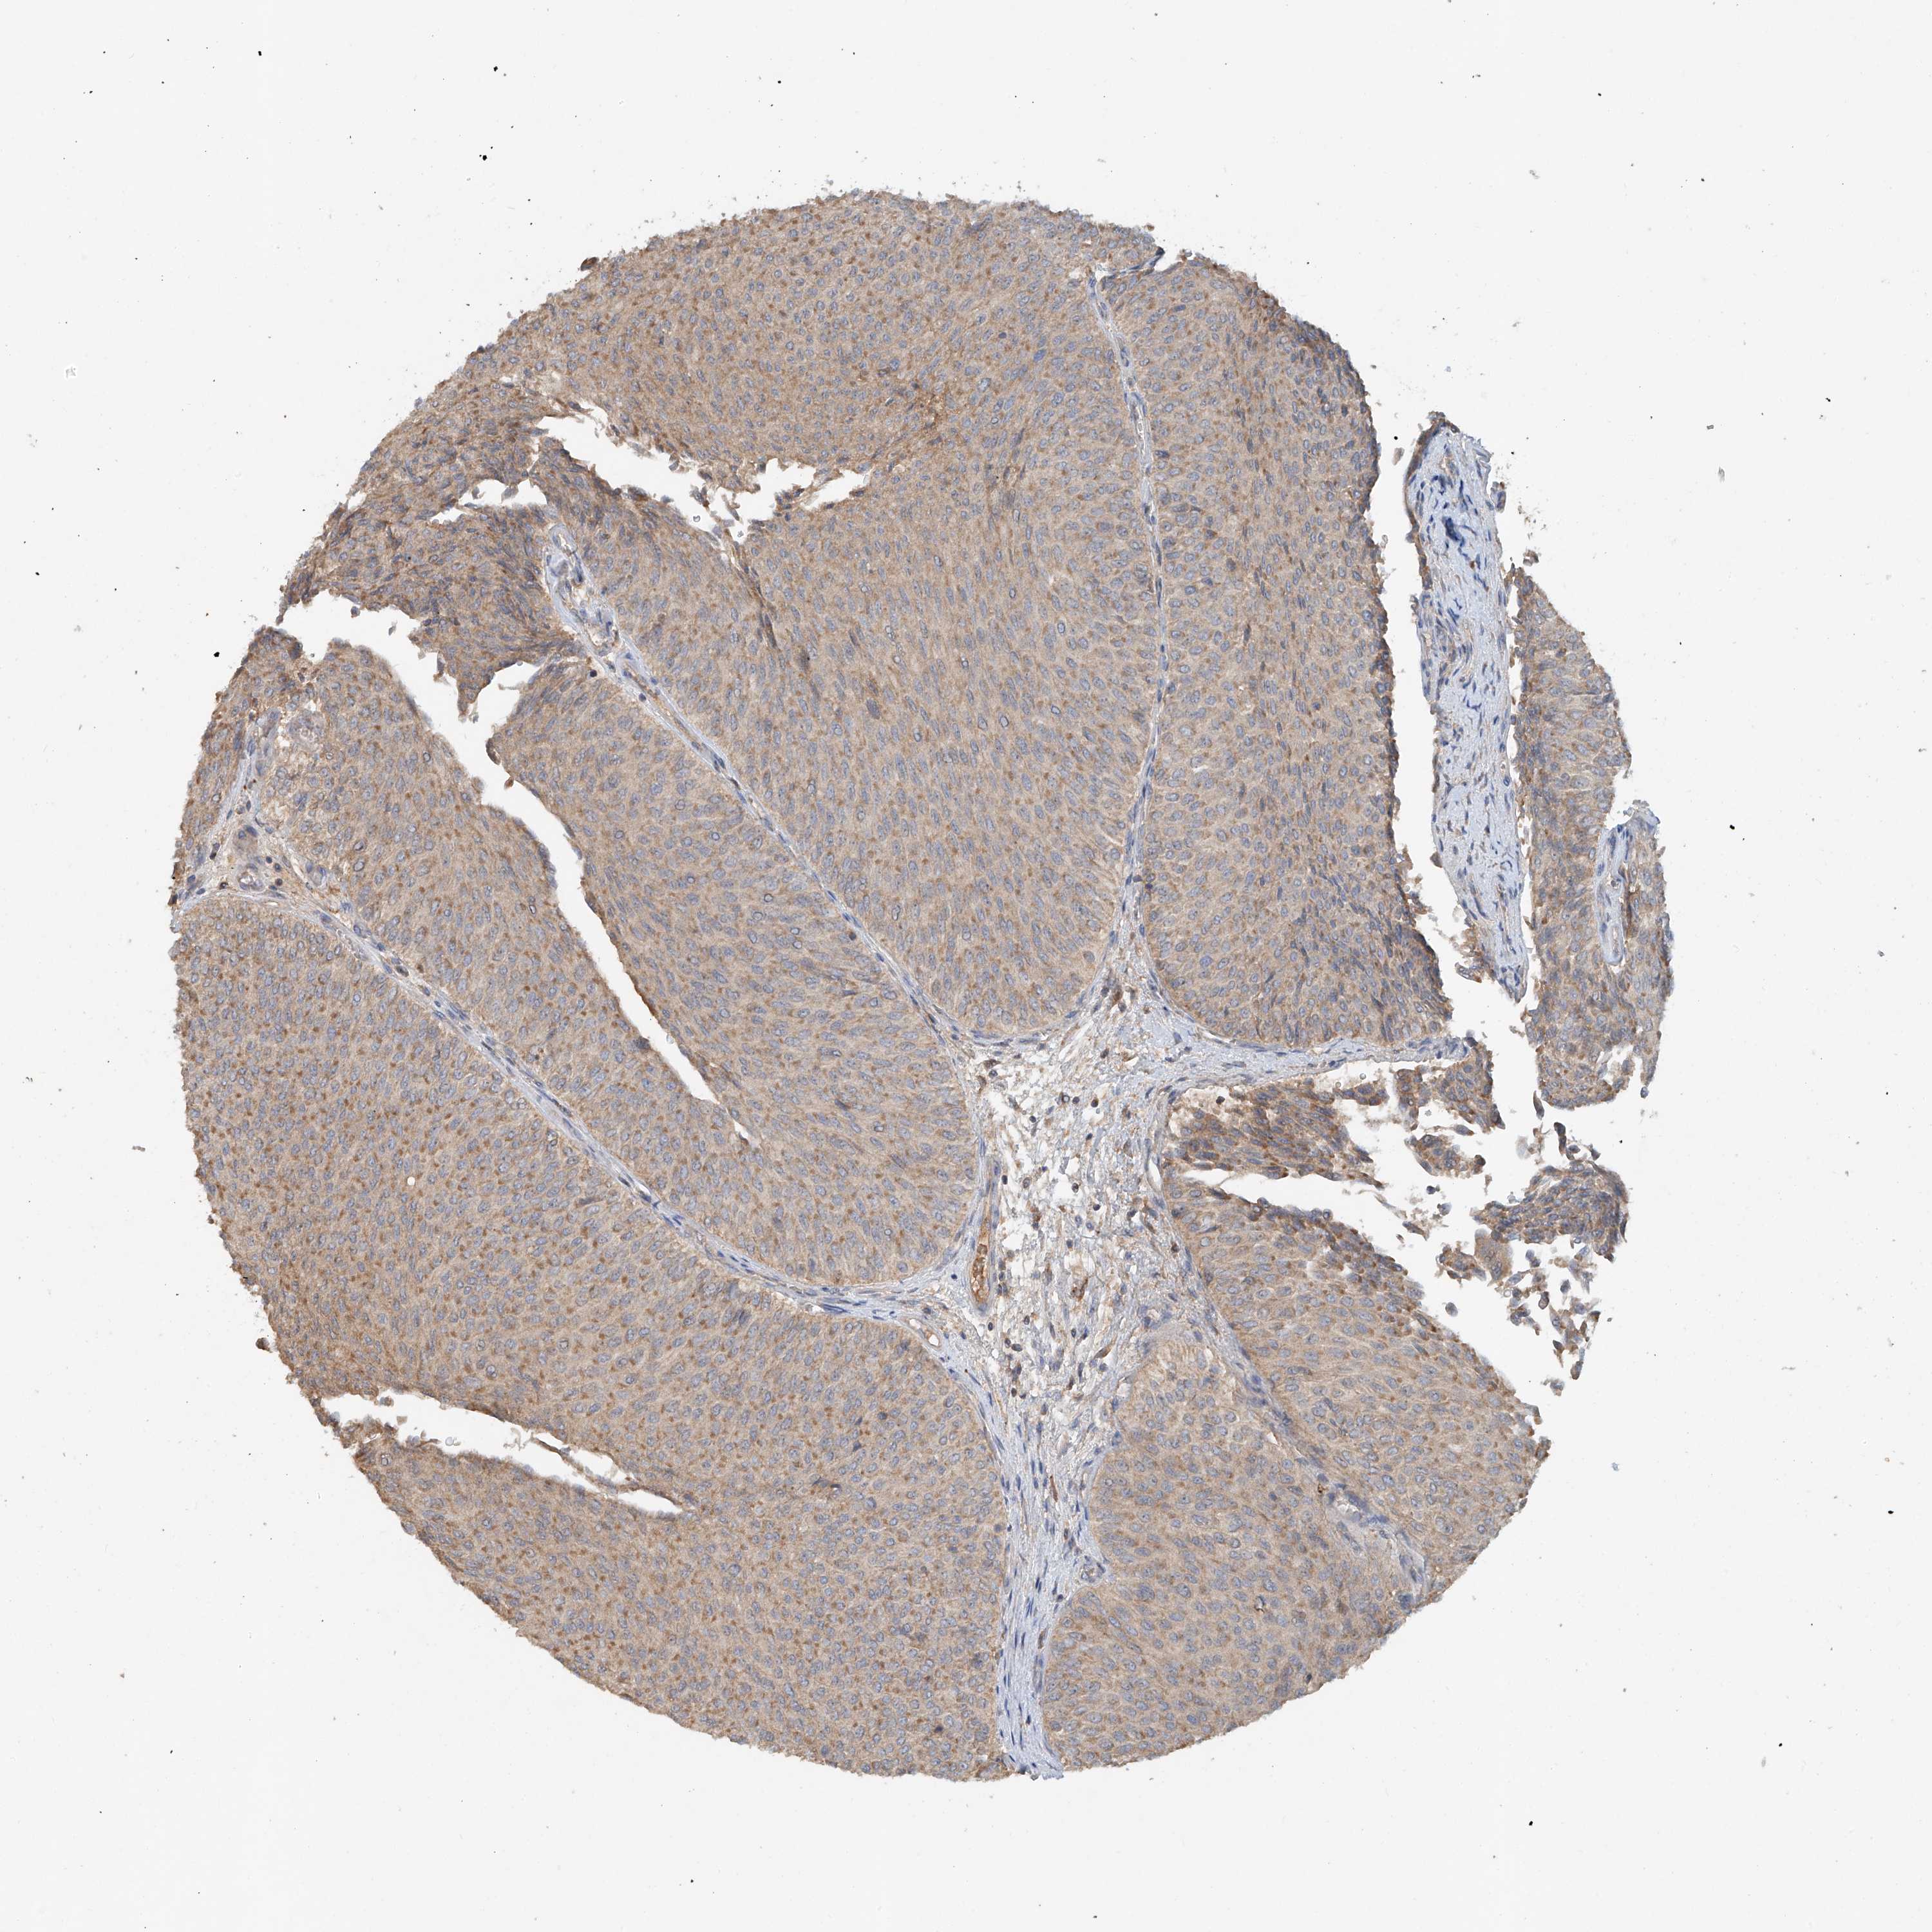

UROTHELIAL CANCER - Protein expressioni

A mouse-over function shows sample information and annotation data. Click on an image to view it in a full screen mode. Samples can be filtered based on level of antibody staining by selecting one or several of the following categories: high, medium, low and not detected. The assay and annotation is described here.

Antibody stainingi

Antibody staining in the annotated cell types in the current human tissue is reported as not detected, low, medium, or high, based on conventional immunohistochemistry profiling in selected tissues. This score is based on the combination of the staining intensity and fraction of stained cells.

Each image is clickable and will lead to virtual microscopy that enables deeper exploration of all samples and also displays staining intensity scores, fraction scores and subcellular localization as well as patient and tissue information for each sample.

Antibody HPA034627

Staining

High

Medium

Low

Not detected

Intensity

Strong

Moderate

Weak

Negative

Quantity

>75%

75%-25%

<25%

None

Location

Nuclear

Cytoplasmic/membranous

Cytoplasmic/membranous,nuclear

Urothelial carcinoma, Low grade

Urothelial carcinoma, High grade